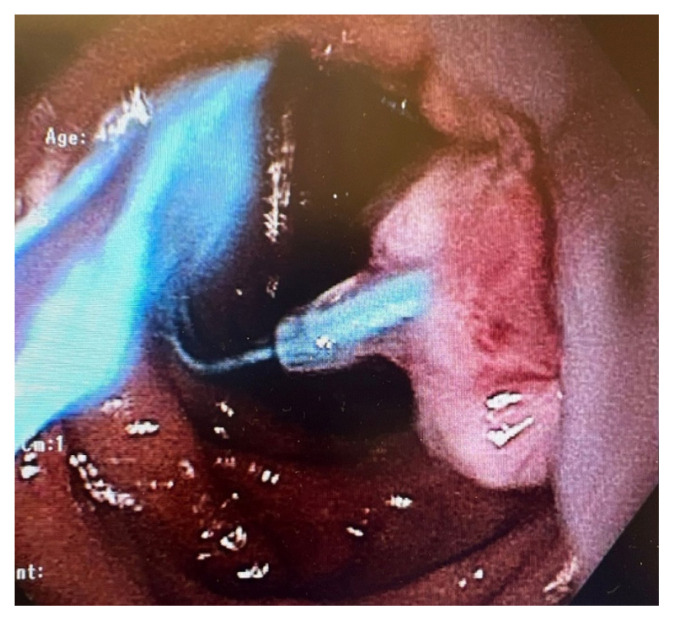

Massive Upper Gastrointestinal Bleeding Secondary to a Large Pedunculated Brunner Gland Hamartoma in the Duodenum.

十二指肠大带蒂布伦纳腺错构瘤继发的大量上消化道出血。